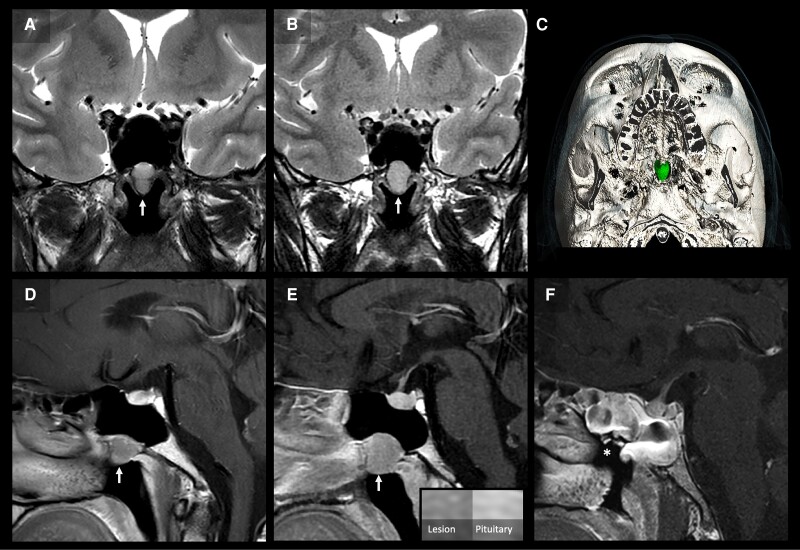

We report a 31-year-old man with diarrhea and tachycardia. Diagnostic workup confirmed raised free thyroid hormones with unsuppressed thyroid stimulating hormone (TSH). Laboratory assay and medication interference were excluded. Consistent with a high glycoprotein hormone α-subunit (α-GSU), the α-GSU:TSH molar ratio was increased. However, anterior pituitary panel testing also confirmed an isolated, raised follicle stimulating hormone (FSH) (17.3 IU/L; reference range, 1.7-8.0). Therefore, interpretation of α-GSU was limited given the co-existent elevated FSH. There was no pituitary lesion on magnetic resonance imaging (MRI) and stimulated TSH was 232% of baseline levels following thyrotropin-releasing hormone (TRH) stimulation, making a diagnosis of TSH-oma less likely. Genetic analysis revealed no pathogenic variants in the thyroid hormone receptor β gene. Due to the persistently elevated FSH, a follow-up pituitary MRI was arranged, which identified a nasopharyngeal mass on the floor of the sphenoid sinus, raising the possibility of ectopic pituitary tissue. The patient underwent endoscopic resection of this lesion, with subsequent normalization of free T4, TSH, and FSH within a few weeks. Histology confirmed a plurihormonal pituitary adenoma with staining for TSH, growth hormone, luteinizing hormone, and FSH. This case highlights the biochemical and radiological challenges of diagnosing ectopic TSH-secreting pituitary tumors.